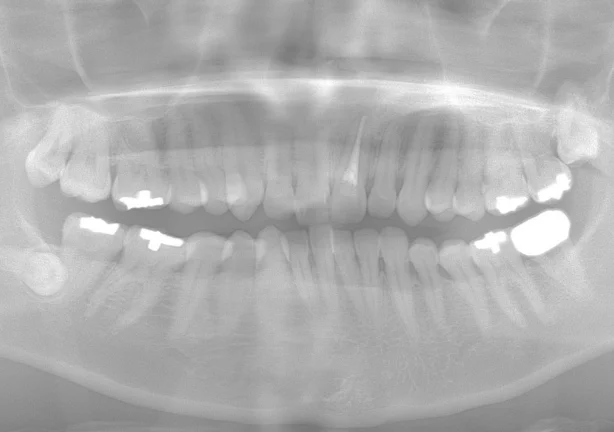

case2

After

治療内容 | 口腔内診査〜カウンセリング 歯周初期治療 仮歯にて噛む位置の再設定 インプラント埋入 仮歯にてインプラントを含めた噛む位置の決定 最終的な被せ物(ジルコニア)の型取り〜装着 |

治療期間 | 1年半 |

治療回数 | 40回 |

リスク | リーニングにこない場合噛み合わせの確認ができないため装着していった人工物が割れてしまう可能性があるため、今後のメンテナンスが必須となる |

費用(税込) | 約¥2,860,000 |